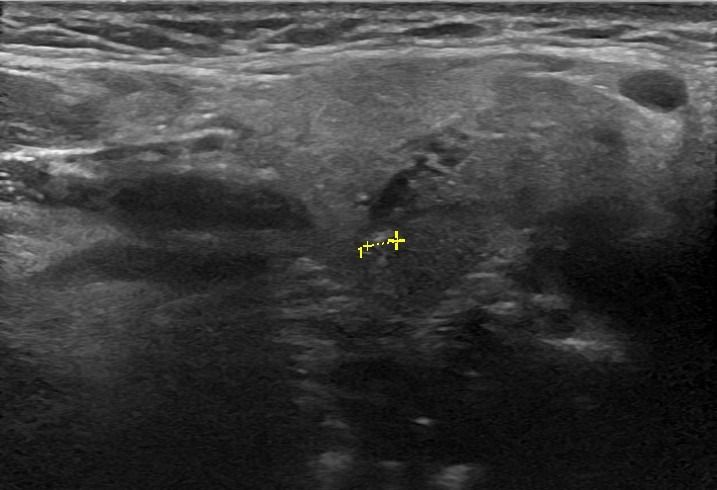

- Διάταση των εκφορητικών πόρων και εντοπισμό λίθων στα πλαίσια σιελολιθίασης και σιελαδενίτιδας

- Εστιακές βλάβες, όπως όγκοι (πλειόμορφο αδένωμα, όγκος Warthin, λέμφωμα)

- Διογκωμένους επιχώριους λεμφαδένες